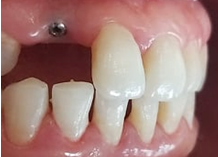

6 months after implant placement: (Figure 9). A second surgical step for the placement of the healing screw to shape the soft tissue, especially the emergence profile.

Figure 9 Placement of the healing screw (6 months after osseointegration).